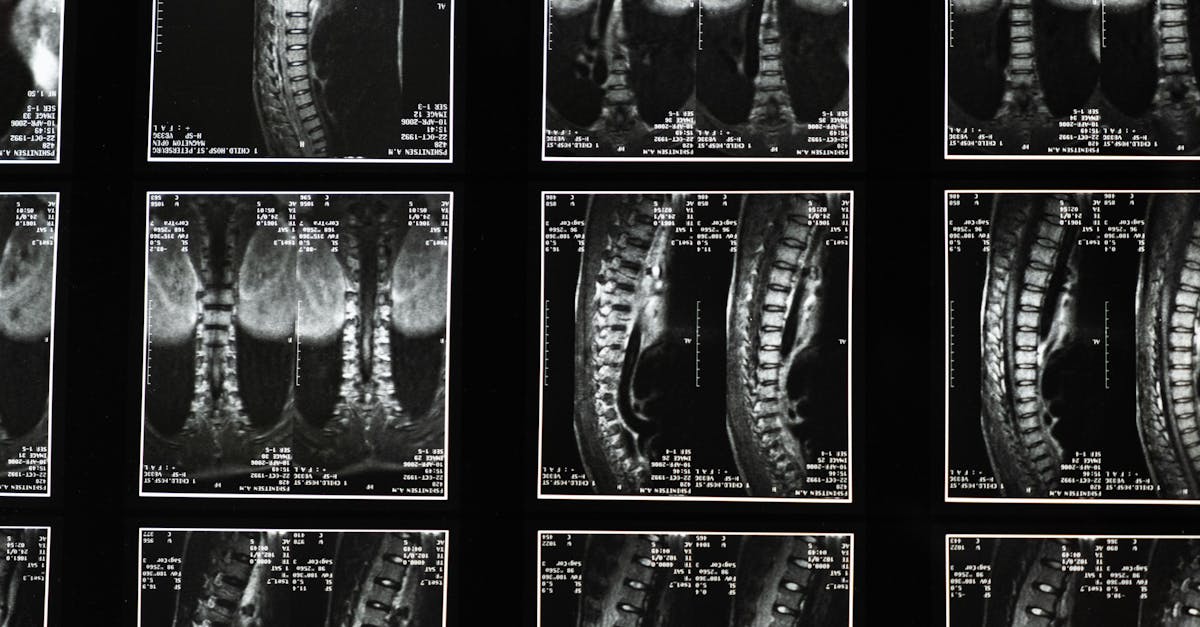

La décompression neurovertébrale est une méthode thérapeutique non invasive qui vise à soulager les douleurs liées à des problèmes de la colonne vertébrale, en particulier ceux causés par la sténose vertébrale et les hernies discales. En créant un espace entre les vertèbres, cette technique permet de réduire la pression exercée sur les disques intervertébraux et les nerfs spinaux. Ce soulagement apporte un soutien précieux à ceux qui souffrent de douleurs chroniques, améliorant ainsi leur mobilité et leur qualité de vie.

Traditionnellement, la gestion des douleurs de la colonne vertébrale impliquait des traitements conservateurs ou des interventions chirurgicales. Toutefois, la décompression neurovertébrale s’est révélée être une alternative efficace, permettant aux patients d’éviter les risques associés aux opérations invasives. À l’aide d’un appareil spécialisé, le traitement applique une traction contrôlée, favorisant l’hydratation et la régénération des disques intervertébraux.

Tout d’abord, la décompression neurovertébrale joue un rôle crucial dans la réduction de la douleur liée à des affections comme la sténose spinale ou les hernies discales. En créant un espace entre les vertèbres, cette technique permet une meilleure circulation des nutriments et des fluides dans la colonne vertébrale, favorisant ainsi une guérison optimale des tissus environnants. Cela se traduit par une diminution significative des symptômes, et par conséquent, une amélioration de la qualité de vie générale des patients.